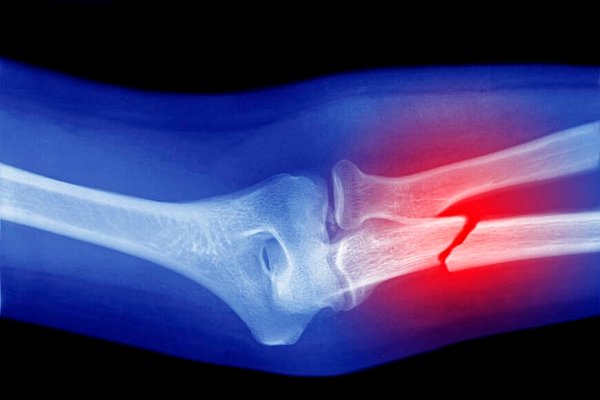

Bu çökme sonucunda sertleşme oluşur. Sonrasında ise kırık kemiğin sabitlenmesi için yumuşak kallus rol alır. Yeni gelişen bu yapı 6 ila 12 hafta arasında daha da sert bir hale gelerek sert kallus adını alır.